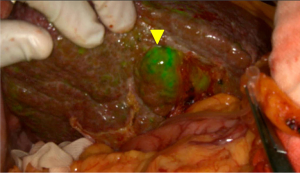

One of the disadvantages of ICG fluorescence imaging-based tumor detection is the relatively high false-positive rate. According to previous reports, out of the lesions newly detected only by fluorescence imaging of resected HCC specimens, 40–50% were non-cancerous lesions, such as regenerative nodules, atypical adenomatous hyperplasia, adenomatous hyperplasia, and bile duct proliferation (10,20). For this reason, additional resection of these lesions should be recommended only when the other diagnostic modalities (re-evaluation of preoperative images, especially MRI, palpation/visual inspection, and/or intraoperative ultrasonography) also support a possibility of malignancy. Figure 2 demonstrates a false-positive nodule detected only by intraoperative ICG fluorescent imaging. The pathological diagnosis was a large cell regenerative nodule.